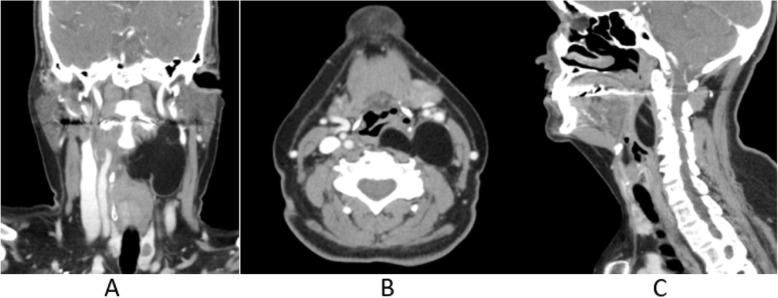

A 66-year-old female presented for a pre-implant CBCT with no history of other complaints or signs/symptoms. CBCT imaging depicts a large, well-defined, low-attenuation/soft tissue density lesion with an undulating appearance extending from the posterior left pharyngeal wall and occluding two-thirds of the airway from C2 to C4. The lesion extends laterally into the left parapharyngeal space and inferiorly beyond the field of view of the study. Evidence of faint internal septations was noted. The patient was immediately referred for an ENT consult. Laryngoscopy, MRI, and contrast-enhanced MDCT imaging were conducted to determine the full extent and nature of the lesion, as well as to potentially plan for biopsy and/or surgical resection. Removal of the lesion was successful, and histopathologic evaluation confirmed lipoma. Periodic follow-up was recommended to monitor for possible recurrence.

一名66岁女性因种植前CBCT检查前来就诊,无其他既往病史或体征/症状。CBCT成像显示一个大的、边界清晰的、低衰减/软组织密度病变,呈波浪状外观,从左咽后壁延伸,阻塞了从C2到C4三分之二的气道。病变向外侧延伸至左咽旁间隙,向下超出研究视野范围。可见微弱的内部间隔迹象。患者立即被转诊至耳鼻喉科会诊。进行了喉镜检查、MRI和增强MDCT成像,以确定病变的全貌和性质,并可能为活检和/或手术切除制定计划。病变切除成功,组织病理学评估证实为脂肪瘤。建议定期随访以监测可能的复发情况。